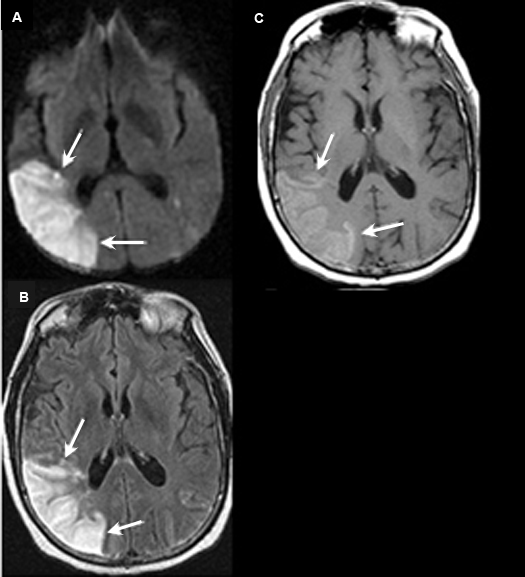

Figure 5 A-C: MR Images

Posterior cerebral artery territory Acute Stroke

Case 5:

Imaging findings: Figure 5 A-C

- Pre-contrast axial T1 wtd. MRI

- Axial flair image

- Post-contrast axial T1 wtd. MRI

Acute infarction is seen involving the left occipital lobe (yellow arrow) and adjacent left temporal lobe (white arrow). The left posterior cerebral artery territory infarction is better seen on flair sequence (Fig. B) than on T1 wtd. pulse sequence (Figs. A, C).